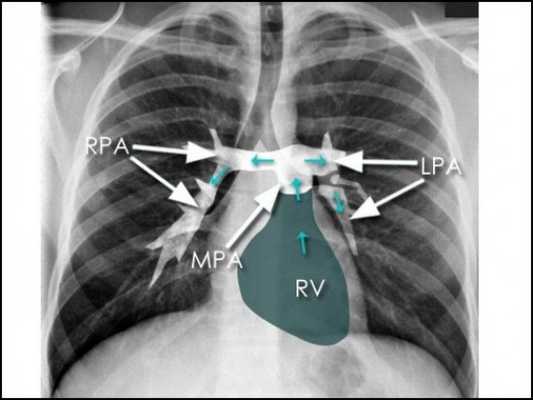

Рентгеноанатомия средостения

На обзорной рентгенограмме органов грудной клетки (ОГК) в прямой проекции органы средостения формируют тень по форме напоминающую неправильную трапецию. Нижняя половина формируется за счет тени сердца, и небольшой участок за счет нижней полой вены. Верхняя половина за счет теней магистральных кровеносных сосудов (верхняя полая вена, дуга аорты, легочная артерия). По бокам средостения визуализируются корни легких, и легочные поля, снизу купол диафрагмы (Рис. 14).

На компьютерных томограммах в аксиальной проекции визулизируются (Рис.7 — 13, 16-19):

1 – Правое легкое

2 – Левое легкое

4 — Левый главный бронх

5 – Правый главный бронх

6 – Непарная вена

7 — Нисходящая часть аорты

8 – Восходящая часть аорты

9 – Левый желудочек сердца

10 – Левое предсердие

11 – Правый желудочек

13 – Легочный ствол, с отходящими от него левой и правой легочными артериями

15 – Плечеголовной ствол

16 – Левая общая сонная артерия

17 – Левая подключичная артерия

18 – Правая общая сонная артерия

19 – Правая подключичная артерия

20 – Верхняя полая вена

21 – Левая плечеголовная вена

22 — Правая плечеголовная вена